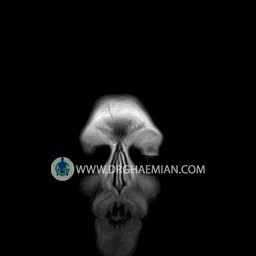

پزشکان اغلب از تصویربرداری ام آر آی برای تشخیص و درمان عارضه های پزشکی که فقط با استفاده از اشعه ایکس یا میدان مغناطیسی و امواج رادیویی قابل مشاهده است، استفاده می کنند. دستگاه ام آر آی تصاویر دقیق از ساختار های داخلی بدن ایجاد می کند. در این کیس نوریت اوربیت چب و سلای خالی بیمار مشاهده می شود.

ORBIT MRI

(with and without contrast)

Technique:Axial T1 , Axial , sagittal , coronal FSE T2 , coronal T1, sagittal fat sat T2 , Axial , sagittal T1 post Gd .

The both orbit are symmetrical and of normal size , with normal development of the orbital cones .

The bony orbital walls show a normal configuration with smooth and, sharp margins .

No foci of bone destruction , no circumscribed expansion of the bony or soft – tissue components of the orbital are evident .

The globes are symmetrical and of normal size and the ocular contents show normal signal characteristics .

The ocular walls are smooth , sharply defined , and of normal thickness .

The retrobulbar fat, ophthalmic vein and lacrimal apparatus are unremarkable .

Evaluable portions of the neurocranium and paranasal sinuses show no abnormalities .

No seen any evidence of ocular herniation

– Small fluid around the left optic nerve with mild edema suggestive for left optic neuritis

– Extension of suprasella cistern to sella with thin pituitary gland in floor of sella ( empty sella )

are seen

REPORTED BY :Dr DrNaser. Ghaemian.